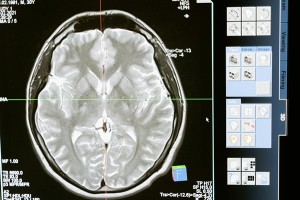

Na de diagnose van de ziekte van Parkinson zijn er medicijnen die de klachten kunnen verminderen. Dit zijn vooral levodopa en middelen die lijken op dopamine (agonisten). Als deze medicijnen niet geleverd kunnen worden, of worden vervangen door een middel van een andere fabrikant, kan dat grote gevolgen hebben.

Overzicht wachttijd voor DBS

De zeven centra in Nederland die DBS‑behandelingen uitvoeren, hebben samen afgesproken hoe zij de wachttijd berekenen. De Parkinson Vereniging vraagt regelmatig bij alle DBS‑centra op hoe lang deze wachttijden zijn.Er zijn twee soorten wachttijden:

• De tijd tussen de verwijzing door je eigen neuroloog en de intake bij de gespecialiseerde neuroloog in het DBS‑centrum.

• De tijd tussen de intake en de operatie. Dit is een combinatie van de doorlooptijd van de uitgebreide screening (meestal 20 tot 26 weken) en de daadwerkelijke wachttijd.